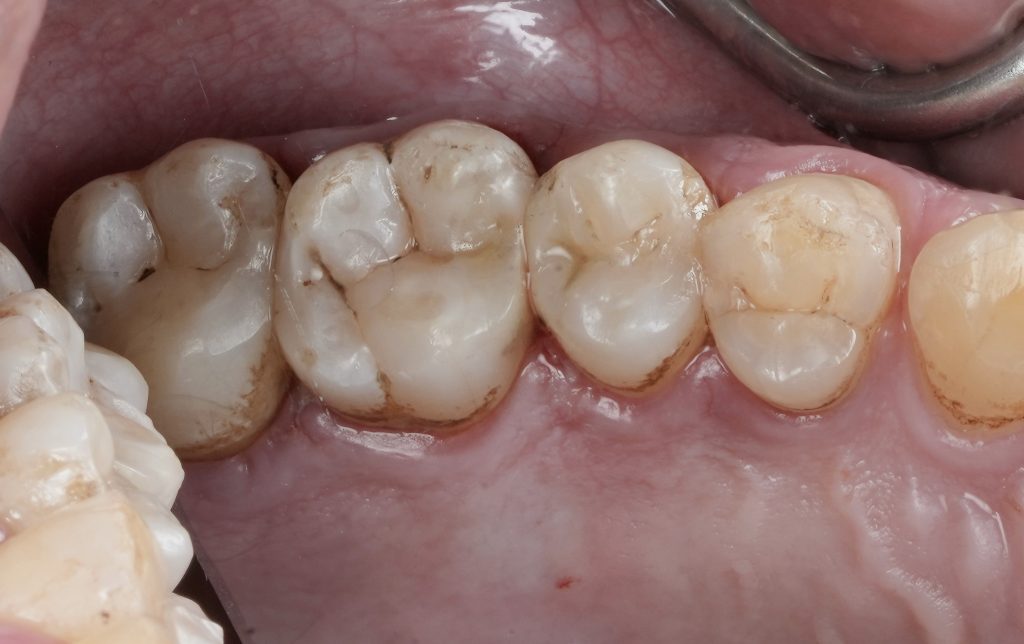

Finishing and Occlusal Adjustment

Following removal of the matrix, proximal contact was verified clinically. Finishing and polishing were performed to refine marginal integrity, smooth proximal surfaces, and re-establish occlusal harmony.

Occlusion was checked in static and dynamic movements to ensure functional stability.

The final restoration demonstrated:

- Tight, anatomically correct proximal contact

- Smooth marginal adaptation

- Preserved pulp vitality

- Natural contour consistent with adjacent teeth

The patient reported immediate comfort with no post-operative sensitivity.